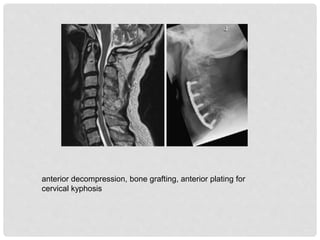

• Treatment

 Operative procedures:

• anterior decompression/corpectomy, strut grafting ± posterior

instrumented stabilization ± posterior column shortening

• Halo traction, anterior decompression, bone grafting, anterior plating

for cervical kyphosis

anterior decompression, bone grafting, anterior plating for

cervical kyphosis